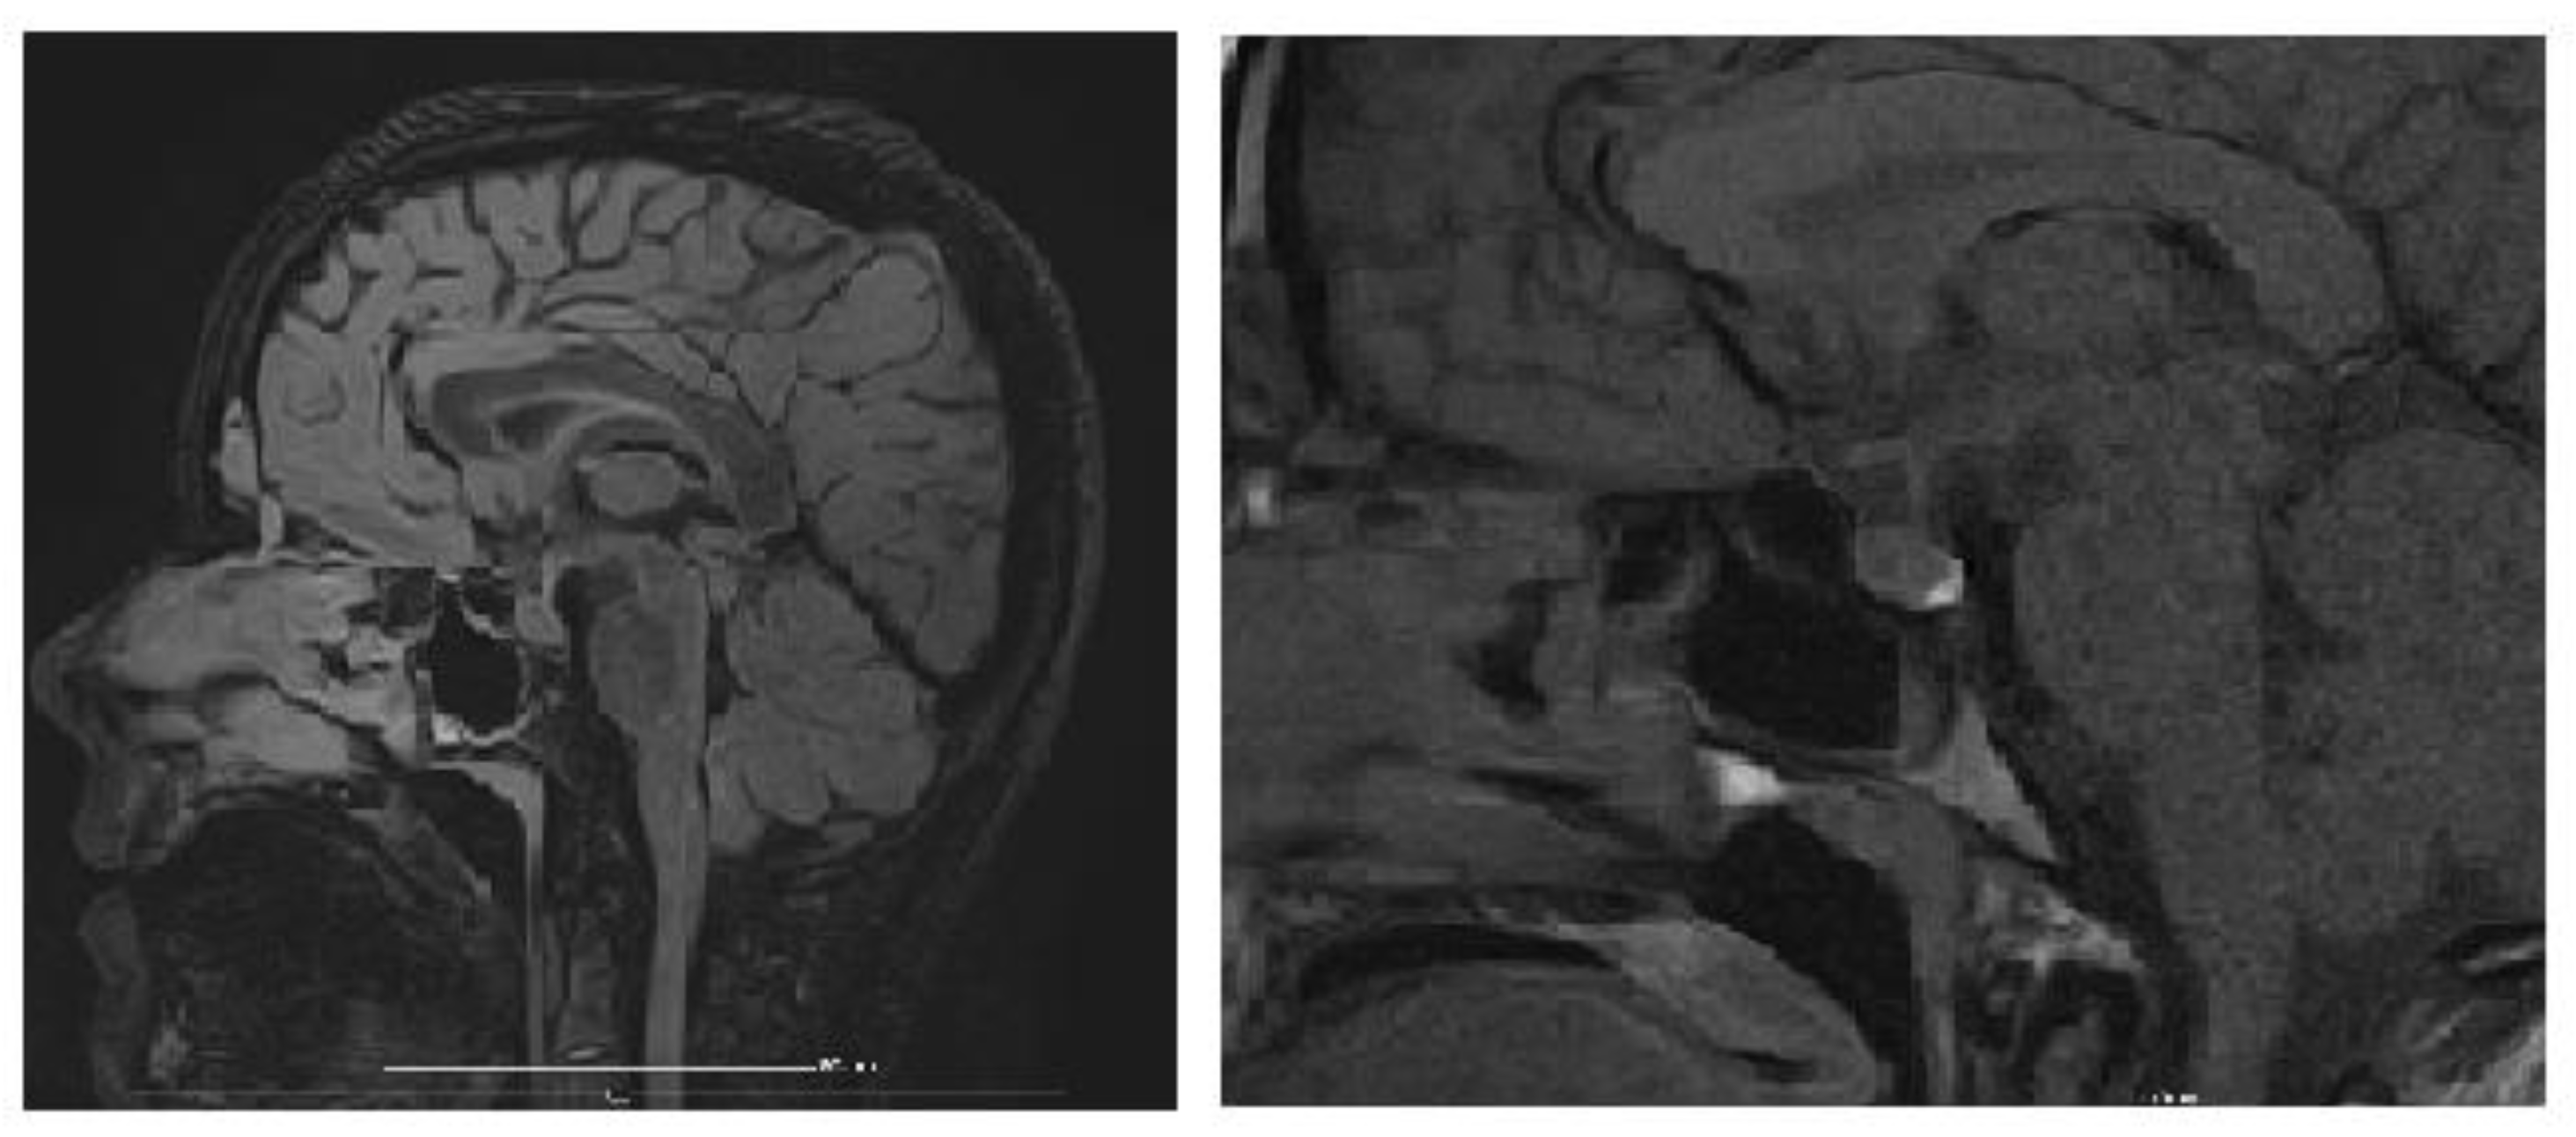

An MRI of the brain and pituitary gland was performed, revealing a pituitary microadenoma (Figure 3), most likely an incidental finding, ruling out other CNS pathologies that would explain chronic hyponatremia (tumor, trauma, vascular acquired conditions, or malformations). The dynamic post-contrast sequence shows a small 3 × 2 mm area with delayed enhancement in the adenohypophysis, considered unrelated to the patient’s symptoms, as pituitary hormone levels were normal, suggesting an incidentaloma.

Figure 3.

Brain MRI (dynamic post-contrast sequence) showing a 3 × 2 mm pituitary microadenoma.